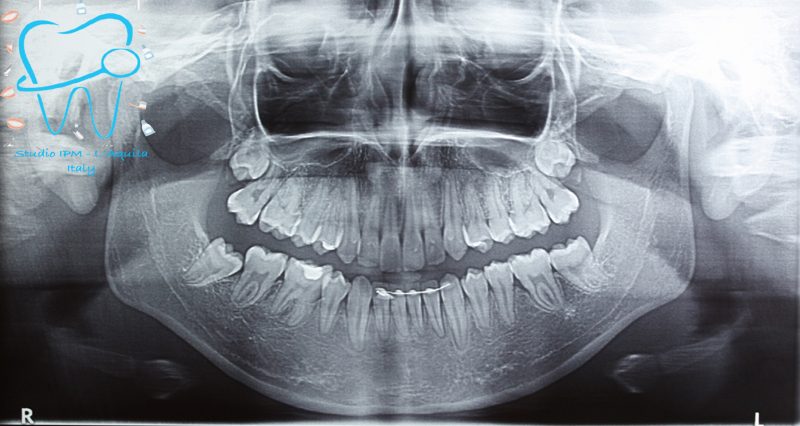

1982 visualizzazioni Una paziente di 12 anni si presenta alla nostra osservazione con una malocclusione in arcata superiore ed inferiore. La situazione appare complicata, oltre che da un affollamento notevole in arcata superiore, dalla agenesia dell'elemento 4.5 e con il 3.6 molto distrutto e difficilmente recuperabile per il futuro in maniera pervedibile. Si decide a questo punto per un trattamento ortodontico fisso con il movimento mesiale degli elementi posteriori e la chiusura degli spazi solo con denti sani e pienamente funzionanti ed evitare successivamente costosi procedimenti protesici.